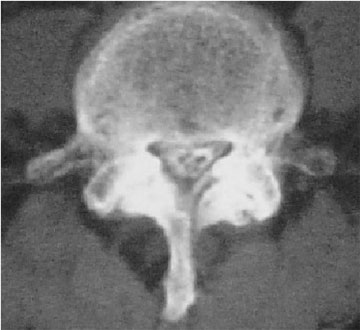

正常脊椎管模型

椎管狭窄症模型

陈旧性椎间盘突出,黄韧带肥厚,椎间关节增大等多种原因导致椎管狭窄压迫神经因而引发腰下肢痛,麻痹,间歇性跛行等症状。